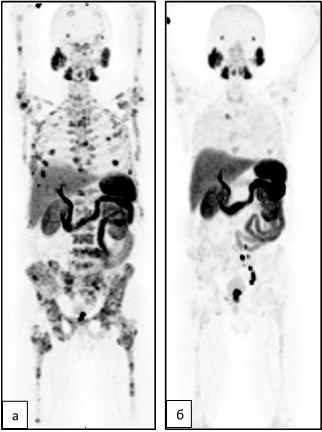

Пациент с диагнозом рак предстательной железы, кастрационно-резистентная форма, метастатическое поражение костей. Назначена радионуклидная терапия 223Ra-дихлоридом. Перед началом и по окончанию 6-го курса терапии была выполнена ПЭТ/КТ с 1818F-ПСМА-1007. В проекциях максимальной интенсивности (MIP) отмечается очаговая гипераккумуляция РФП в костных очагах (а) с выраженной тенденцией к снижению по завершению терапии 223Ra-дихлоридом (б).